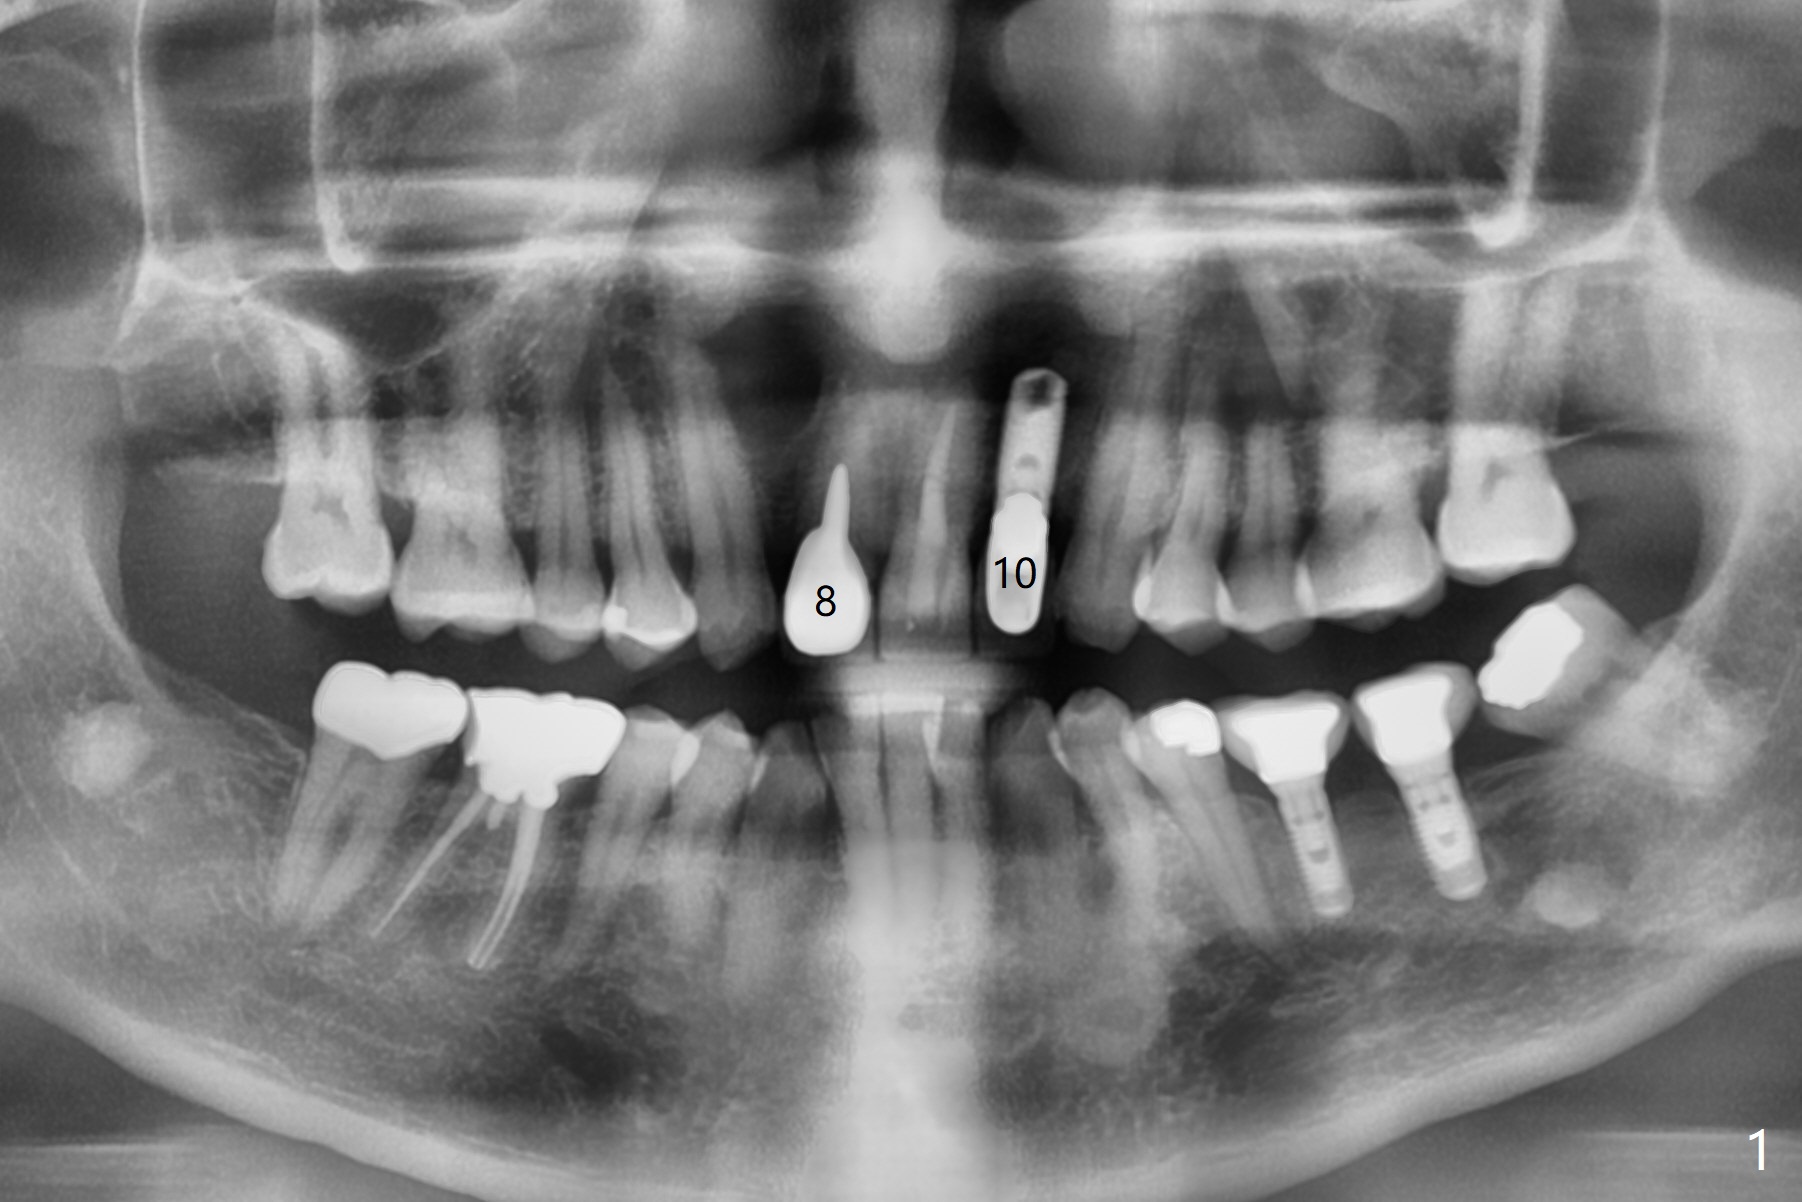

A 56-year-old man presents to clinic for recementation of the crown/post at #8, which is non-salvageable (Fig.1). There are 3 existing implant crowns, including #10. The implant at #10 (4.5 mm in diameter) was placed buccally, although there is no infection (Fig.2). To prevent this complication, a smaller implant should be placed palatal (Fig.3). In addition, the tooth #7 is missing. Instead there is a labial concavity (Fig.3 *). Use a temporary abutment for provisional.